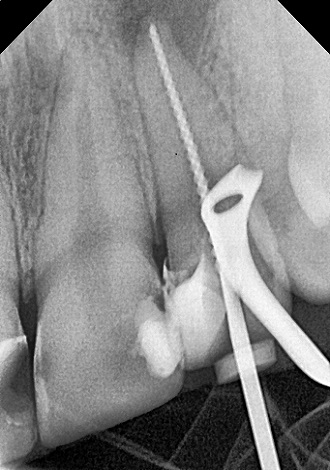

5. визначити глибину каналів зубного кореня;

6. механічна розробка каналів;

7. хімічна обробка каналів;

8. герметична обтурація.

Якісно запломбовані кореневі канали є основою довговічності. Тому очищення і пломбування кореневих каналів в «Домі Стоматології» приділяється особлива увага! Після пломбування кореневих каналів проводиться контроль якості пломбування за допомогою знімка.